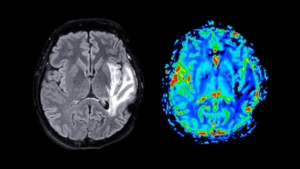

A comprehensive new investigation has illuminated a significant correlation between prolonged exposure to atmospheric pollutants and an...

New scientific inquiry originating from the NYU School of Global Public Health indicates a potential nexus between...